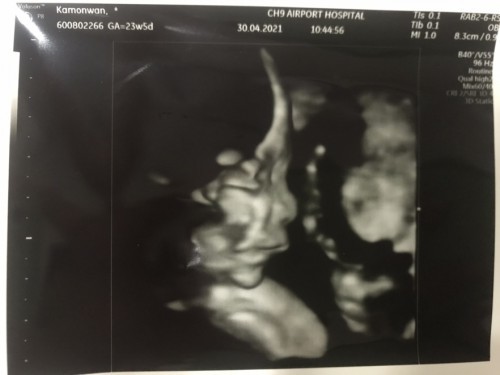

สวัสดีครับผม24สัปดาห์น้ำหนัก600g ความยาว 30 cm.แล้วนะครับเห็นหน้าผมกันไหม🥰